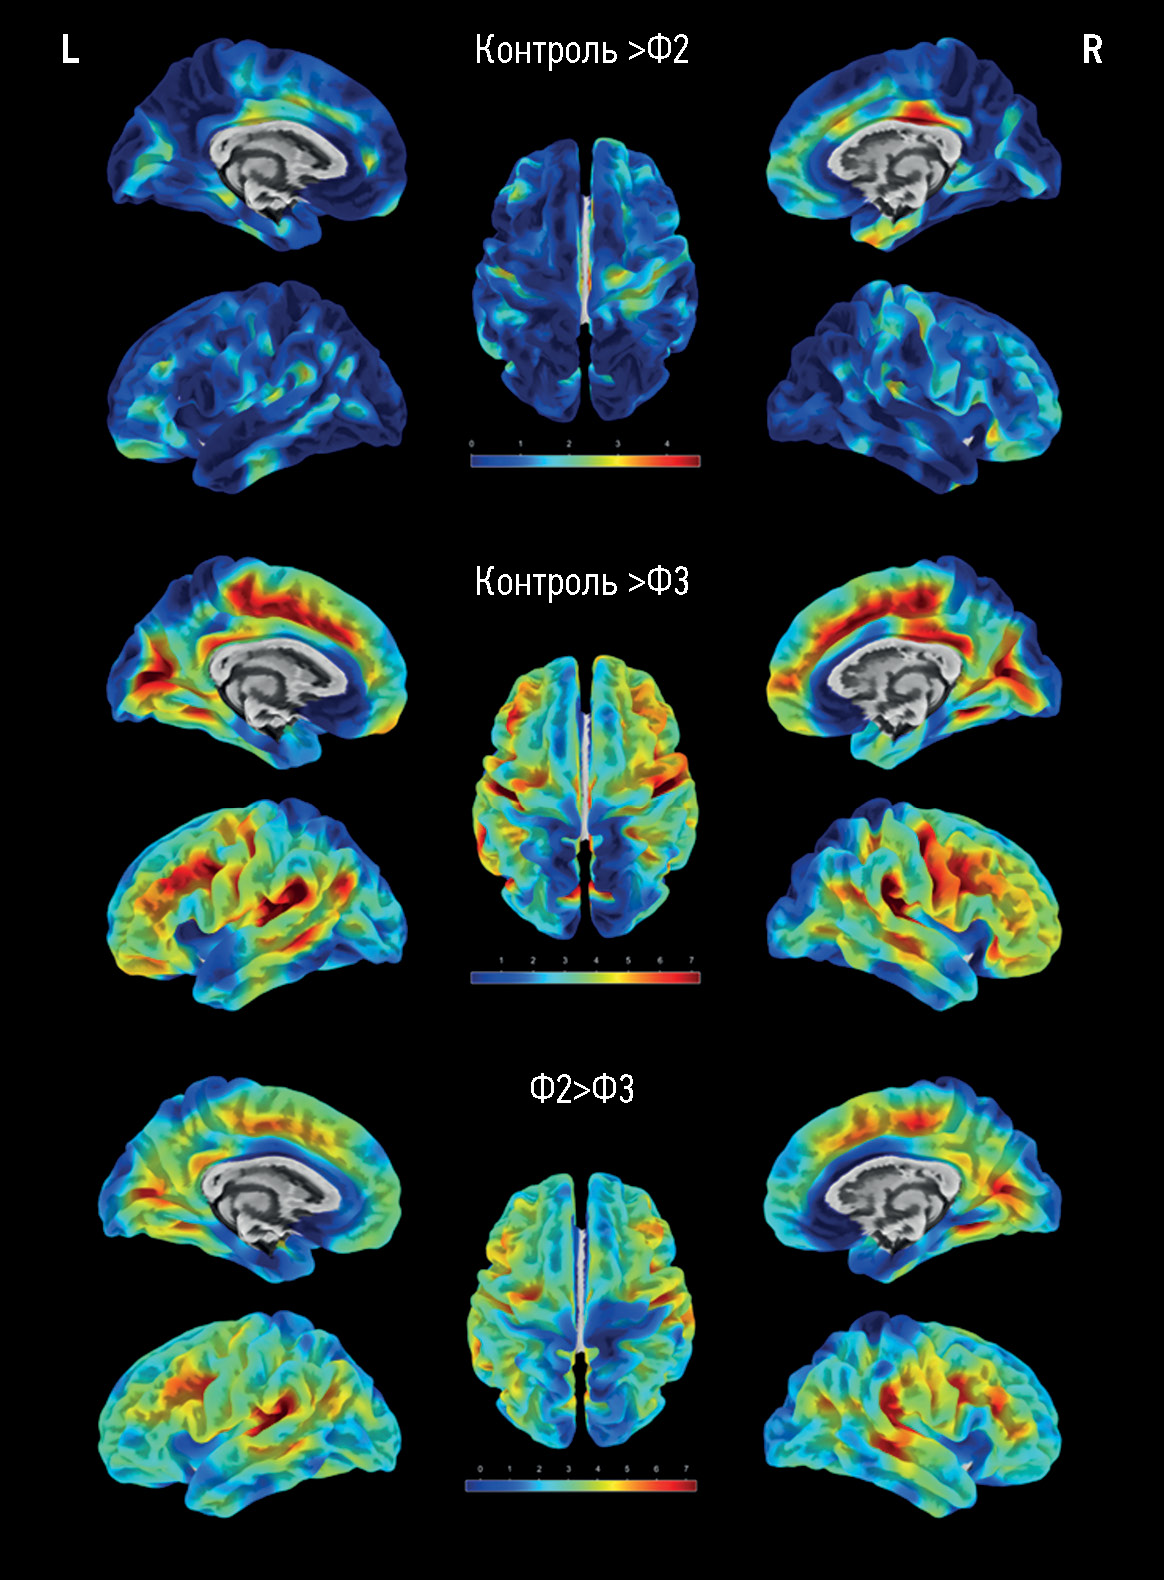

对年龄依赖性脑微血管病患者在不同严重程度认知障碍下的大脑半球皮层表面的形态测量

摘要

论证。散发性年龄依赖性脑微血管病占到所有痴呆病例的45%,在评估其认知障碍的基础方面结构性磁共振成像分析发挥着关键作用。在脑微血管病患者中,使用磁共振形态测定法得出的不同结果,需要对其进行广泛的研究,并与临床数据进行比较。

研究目的 — 使用表面形态测量法评估脑微血管病患者认识障碍的大脑萎缩特征

材料和方法。对脑微血管病变和不同严重程度认知障碍(主观、中度和痴呆)的患者,以及一组性别和年龄相当的志愿者进行前瞻性研究和评估。评估包括根据磁共振成像数据分析大脑微血管病的症状,计算大脑微血管病的总指数,并通过表面形态测量法处理 T1mpr图像,对大脑进行总体和区域定量评估,包括大脑半球皮层的厚度。

结果。主要组包括173名脑微血管病患者,对照组包括47名健康的志愿者。随着大脑结构变化和认知障碍的严重表现程度增加,局部区域的皮质厚度也出现了类似的显著下降(p < 0.05),这些区域包括:扣带回,主要是其后部;额叶的内侧和中间部分;岛叶皮质的各个部分;颞顶叶区域(特别是额上回)。脑微血管病患者大脑本身的体积(总体积、灰质和白质体积)仅与对照组有显著差异,而不同认知障碍严重程度的患者组之间则无显著差异。在痴呆与中度认知障碍组、痴呆与主观认知障碍组之间,高密度信号白质体积存在显著差异(P<0.0001)。

结论。在研究期间获得的数据证实,脑微血管病萎缩的继发性/混合性。皮质明显变薄的区域各不相同,这种情况限制了按照萎缩程度来确定大脑微血管病认知障碍的病情发展状态。这使得皮质的定量测量仅作为评估脑微血管病程的预后辅助方法。